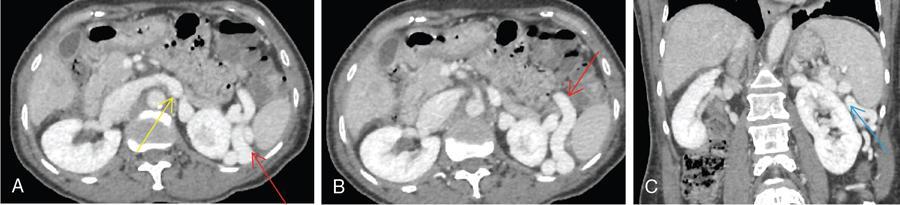

Shrinivas B. Desai, Ritu K. Kashikar, Aman Snehil, Ajay Jhaveri Cirrhosis is a late stage of irreversible scarring of the liver causing abnormality in liver structure and function. Multiple conditions and factors can cause repeated liver damage and scarring ultimately leading to cirrhosis. The most feared complication of liver cirrhosis is the development of hepatocellular carcinoma (HCC). Portal hypertension (PHT) is seen with a variety of conditions but cirrhosis happens to the most important cause. Imaging plays a vital role in noninvasive diagnosis and treatment planning of both cirrhosis and PHT. Liver imaging reporting and data system (LI-RADS) is a standardized reporting system assigning an observation risk of representing HCC. This chapter focuses on discussing aetiologies and imaging of PHT with a lucid review of L1-RADS 2018 version. The portal blood circulation is a unique circulatory circuit as it connects two capillary beds between the liver parenchyma at one end and the gastrointestinal tract and splenic parenchyma at the other end. The portal system ramifies in the liver and ultimately ends in the hepatic sinusoids from where the blood ultimately drains into the inferior vena cava (IVC). The portal vein (PV) originates from the capillary beds in the stomach, intestine and the spleen. The main PV is formed behind the neck of the pancreas by the confluence of the superior mesenteric vein (SMV) and splenic vein. It continues to the porta hepatis where it bifurcates into the left and right branches as it carries nutrient rich but oxygen poor blood to the liver (Fig. 9.9.1). The PV makes up for 75%–80% of the liver’s blood supply while the hepatic artery which arises from the celiac trunk makes up for the remaining 25%. A pathological increase in the portal venous pressure is referred to as PHT. PHT is most often a sequel of chronic parenchymal liver disease and leads to major life-threatening complications due to bleeding from the collateral circulation (most commonly oesophageal varices). Direct measurement of portal pressure (PP) is invasive and often not feasible in most patients and thus imaging plays an important role in the diagnosis of PHT and its complications. The normal portal venous pressure ranges between 5 and 10 mmHg, which is the equivalent of 7–14 cm H2O. The normal hepatic venous pressure gradient (HVPG) is the pressure gradient between the PV and the IVC, is typically 1–5 mmHg. Presence of PHT is indicated by a wedged hepatic venous pressure of more than 5 mmHg. Other definitions include a splenic pressure of more than 15 mmHg or an intraoperative PP of greater than 30 cm H2O. The complications of PHT are seen when HVPG is greater than 10 mmHg and hence this value defines clinically significant PHT. Variceal bleeding is seen with a pressure greater than 12 mmHg. In ideal conditions, the portal circuit is a high flow, low resistance circuit as it has to allow substantial flow rates of 700–1000 mL/min to the hepatic parenchyma from the gastrointestinal tract. Anatomical changes in the organization of the hepatic lobule can result in rise in the portal resistance. These can occur in the form of collagen deposition in the space of Disse, fibrotic scars formed due to regenerative nodule (RN) formation, loss of normal elasticity of the endothelium and distal venous thrombosis. Changes in splanchnic haemodynamics due to factors that increase splanchnic blood flow and increase in intrahepatic vascular resistance due to transformation of stellate cells into myofibroblasts also contribute to the increase in PP gradient. In Western countries, alcoholic cirrhosis and viral cirrhosis are the leading causes of PHT and oesophageal varices. The viral causes form majority of cases leading to cirrhosis and PHT in the Far East and Middle Eastern countries while Schistosomiasis remains an important cause in the African countries. Worldwide, nonalcoholic steatohepatitis (NASH) and hepatitis C are the emerging causes of chronic liver disease (CLD) and PHT. PHT can be classified as cirrhotic and noncirrhotic depending on whether it is associated with cirrhosis or not. This distinction is important as noncirrhotic causes like PV thrombosis are at high risk of development of bleeding but tend to have a better chance of surviving a variceal bleed than a patient with decompensated alcoholic cirrhosis due to preserved hepatic synthetic functions in the former. PHT can also be classified on the basis of the location of the pathology into prehepatic, hepatic and posthepatic causes. Hepatic causes can further be divided into presinusoidal, sinusoidal and postsinusoidal. The causes of portal hypertension have been denoted in Table 9.9.1. The direct measurement of the PP by measuring the HVPG is invasive, expensive not readily available in all patients. Thus, imaging plays an important role in the diagnosis of PHT. Various modalities are used for the imaging diagnosis of PHT. Ultrasonography (USG) and Doppler evaluation have the advantage of being inexpensive, readily available and bedside modality (Table 9.9.2). The role of ultrasound and Doppler in imaging of PHT is to: Grey scale imaging is useful in evaluating the splenoportal anatomy. The evaluation should begin with the liver morphology. Signs of cirrhosis like nodularity of the liver surface with relative atrophy of the right lobe and prominence of the left lobe and caudate should be looked for. Hepatic echotexture appears coarse and more echogenic (Table 9.9.3). Increase in portal venous diameter is a sign of PHT (Fig. 9.9.2). Portal venous diameter of more than 13 or 15 mm has low sensitivity for diagnosing PHT of only 40%–12.5%, respectively. Absolute measurement of the portal diameter as a sign of PHT is also fallacious as in presence of collateral circulation or hepatofugal flow; there may actually be a decrease in the PV diameter. Therefore, a more accurate sign is respiratory variation of PV diameter. An increase in PV diameter of less than 20% with deep inspiration has been reported to indicate PHT with a sensitivity of 80% and specificity of 100%. This has been reported to be an accurate indicator of cirrhosis. Hepatic vein straightness, uniformity of vein wall echogenicity and visualization of at least 1 cm segment of the hepatic vein are the parameters used for evaluation. Splenomegaly is defined as bipolar splenic diameter of greater than 12 cm or largest splenic cross-sectional area passing through the hilum of greater than 45 cm2, and occurs secondary to PHT (Fig. 9.9.3). A total of 65%–80% patients with cirrhosis have splenomegaly on ultrasound. Patients with cirrhosis due to viral hepatitis and primary biliary cirrhosis show splenomegaly more frequently than those with alcoholic cirrhosis. This is an accurate sign of PHT. USG is extremely sensitive with respect to detecting subclinical ascites. Perihepatic space is the most usual site of visualization of minimal ascites. In normal subjects, this ratio is approximately 0.07 and a value above 0.1 suggests the diagnosis of PHT with a 95% sensitivity and specificity. The normal spectral waveform of the hepatic artery is a low resistance flow pattern with forward flow in diastole and a resistivity index in the range of 0.5–0.7. In PHT, the resistivity index of the hepatic artery increases with high resistance flow pattern due to increased peripheral vascular resistance. Resistance index (RI) > 0.78 in the intrahepatic branches of the hepatic artery has been reported to have a sensitivity of 50% and a specificity of 100% for the detection of PHT (Fig. 9.9.11). Pulsatility index (PI) > 1.05 suggests severe PHT with a sensitivity of 86% and specificity of 88% (Fig. 9.9.11). Patency of hepatic veins should be evaluated to rule out Budd–Chiari syndrome as a cause of PHT. The normal hepatic venous waveform (HVW) reflects right atrial activity and this results in a triphasic waveform with one positive and two negative waves. In PHT, this waveform becomes monophasic or biphasic. A monophasic HVW has a sensitivity and specificity of 74% and 95%, respectively, in the diagnosis of severe PHT (Fig. 9.9.12). Dilatation of the splanchnic veins – the SMV and the splenic vein – more than 11 mm are suggestive of PHT with a sensitivity and specificity of 72% and 100%, respectively. A reduction in the respiratory variation of the splenic vein and SMV to less than 40% had a sensitivity and specificity of 79.7% and 100%, respectively, for the diagnosis of PHT (Fig. 9.9.13). The splenic artery reveals an increase in the resistivity index and an RI of >0.63 and a PI of >1 have a sensitivity and specificity of 84.6% and 70.4% for the diagnosis of PHT. Presence of portosystemic collaterals like patent paraumbilical vein, dilated left gastric and short gastric veins are 100% specific sign for PHT (Figs. 9.9.14–9.9.16). Recanalization of the paraumbilical vein, known as the Cruveilhier–Baumgarten syndrome is observed in 43% of patients with PHT, and this is the easiest collateral to assess during the US examination. Various portosystemic collaterals that occur in PHT have been discussed in details in subsection on CT findings in PHT. No Doppler parameter is considered reliable enough to measure PP with sufficient accuracy for use in clinical practice. Oesophageal varices are often present in patients with portosystemic collaterals. Appearance or increase in number of collaterals along with splenomegaly has a high association with variceal formation and growth. USG helps in diagnosis of prehepatic causes like portal stenosis or thrombosis by demonstrating the patency and morphology of the splenoportal system. Arteriovenous fistulae and tumours causing vascular thrombosis as aetiology can be readily detected. USG helps in diagnosis of features of cirrhosis and thus helps differentiate noncirrhotic causes of PHT. USG allows diagnosis of fatty liver disease, which is an emerging cause of cirrhosis. Among the posthepatic causes, USG aids in establishing the diagnosis of Budd–Chiari syndrome by demonstrating the patency and morphology of the IVC and hepatic veins. Owing to the inability of CT to detect flow direction, portal flow rates or pressure gradients, CT is not the primary modality in diagnosis of PHT. Similar to USG dilatation of portosystemic system is a feature of PHT (Fig. 9.9.17). Changes in cirrhosis if present can be seen in the form of surface nodularity, nodules and fibrous septae. CT plays an important role in diagnosis of portal venous thrombosis and evaluating its extent. An acute thrombus is seen as a hypodense filling defect in the vessel causing distension of the venous lumen. Surrounding fat stranding can be seen. A chronic thrombus appears as an eccentric filling defect usually along the wall and is often associated with decrease in vessel diameter. Calcification may be seen in chronic thrombi. Multidetector computed tomography (MDCT) is a useful tool to evaluate portosystemic collateral circulation and recognize complications of PHT. 3D angiography can help understand portal venous and complex variceal anatomy and plan treatment. The various portosystemic collaterals are discussed below. They can be classified into those draining into superior vena cava (SVC) and those draining into the IVC. Magnetic resonance imaging (MRI) is a noninvasive modality used in the evaluation of PHT without the use of ionising radiation. It provides evaluation of parenchymal abnormalities, collaterals and characterization of tumours (Fig. 9.9.28). Spin echo sequences allow characterization of liver masses and liver parenchyma. Loss of flow void allows for detection of thrombosis. Time-of-flight (TOF) angiography is useful in assessing the portal venous system and allows for successful detection of PV thrombosis. The disadvantages of TOF are motion artefacts caused by breathing, long acquisition times and incomplete coverage of the portal venous system. Novel imaging techniques include phase contrast, T1 mapping and magnetic resonance elastography (MRE). The advantage of phase contrast over TOF imaging is that phase contrast imaging acquires information regarding the flow direction in addition to the information regarding the flow velocity. On-phase contrast images signal within vessel is hyperintense when flow is cranial and hypointense when flow is caudal. Look-Locker imaging technique using gradient echo (GRE) MRI sequences with inversion recovery pulse is used to quantify fibrosis by measuring precontrast T1 relaxation times. Interventions in PHT can be aimed at diagnosis or more commonly at management of complications of PHT. HVPG measurement, which is the gold standard for the diagnosis of PHT, can be achieved through cannulation of the PV. Transjugular hepatic biopsy is another diagnostic invasive technique that also allows indirect measurement of PP. Disadvantages include deterioration of hepatic function caused by diversion of portal venous blood flow and shunt dysfunction. TIPSS is contraindicated in patients with congestive heart failure, severe pulmonary hypertension, severe tricuspid regurgitation and hepatic failure. In this technique, a catheter is advanced from the femoral vein into the outlet of the gastrorenal, usually in the region of the left renal vein. The shunt is then occluded with a balloon and sclerosant is injected retrograde to occlude the gastric varices. Histological development of RNs surrounded by fibrous septae in response to chronic liver injury, progressing PHT and end-stage liver disease is termed as cirrhosis. Although initially considered an end-stage phenomenon in CLD, recent evidence suggests that the histological fibrosis can be reversible in early stages with the initiation of specific therapies, for example, in viral cirrhosis with the initiation of antiviral therapy. The one-year mortality rate in cirrhosis varies widely from 1% to 57% depending on the occurrence of complications. Cirrhosis can have a wide variety of causes ranging from congenital to acquired and infectious to noninfectious. It is also a major aetiologic risk factor for the development of HCC. Imaging plays an important role in aetiologic diagnosis of this diverse entity as well as in the diagnosis and management of its complication and surveillance for oncological transformation.

CT scan